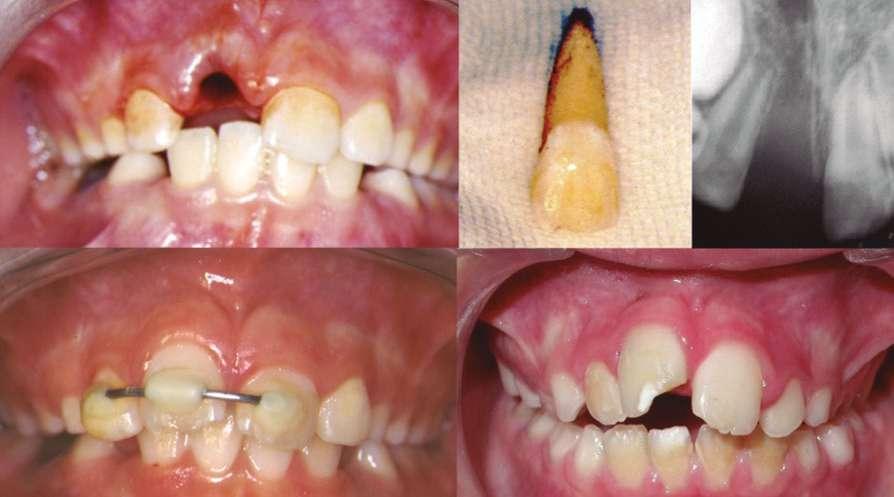

Imágenes 1 y 2. Caso de paciente de 8 años, sexo masculino. En tratamiento se pueden ver los cambios estructurales y oclusales al modificar las funciones de respiración y posición lingual con sistema miofuncional, en 5 meses.

1 2